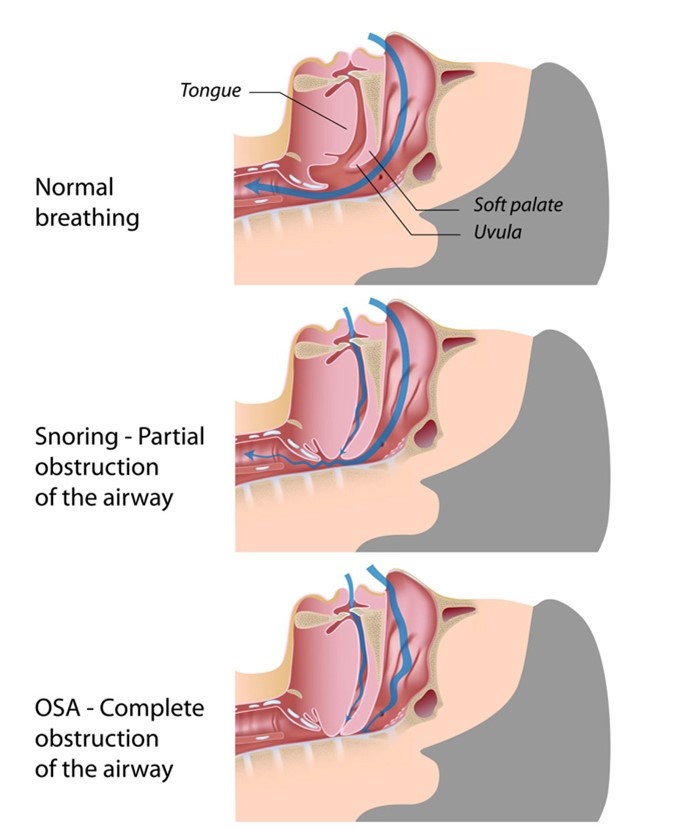

Obstructed breathing can result from abnormal structures in the back of your throat. That includes poor muscle tone, bulky throat tissue, a long soft palate, or a long uvula.

The “uvula” is that part of the fleshy extension of the back of your soft palate which you can easily visualize when your mouth is wide open which hangs above the throat. It looks like a “punching bag” hanging in the back of your throat. It is made of connective tissue and small muscle fibers and secretes saliva to keep your throat well lubricated.

As illustrated, at night, when you are trying to sleep, your tongue and pharyngeal muscles may fall backwards due to size and poor muscle tone, consequently causing a Partial obstruction – that causes Snoring.

When there is Complete obstruction, Sleep Apnea results.